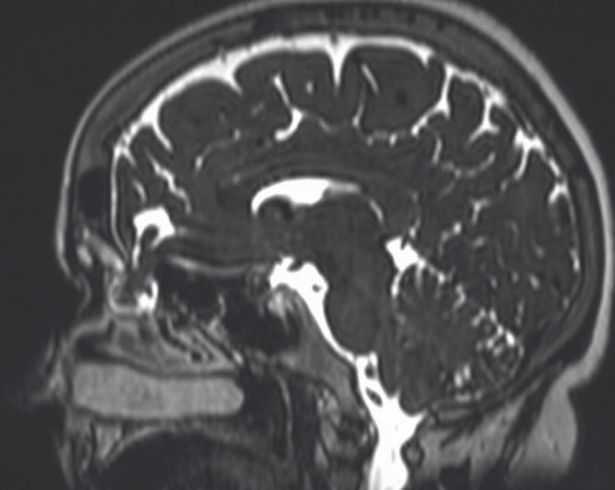

H ακτινογραφία της άτυχης γυναίκας

Τα οστά του κρανίου στο σημείο εκείνο ήταν σπάσει ελαφρώς με αποτέλεσμα τα εγκεφαλικά υγρά να τρέχουν στην μύτη.

Το σημείο που έσπασε το οστό